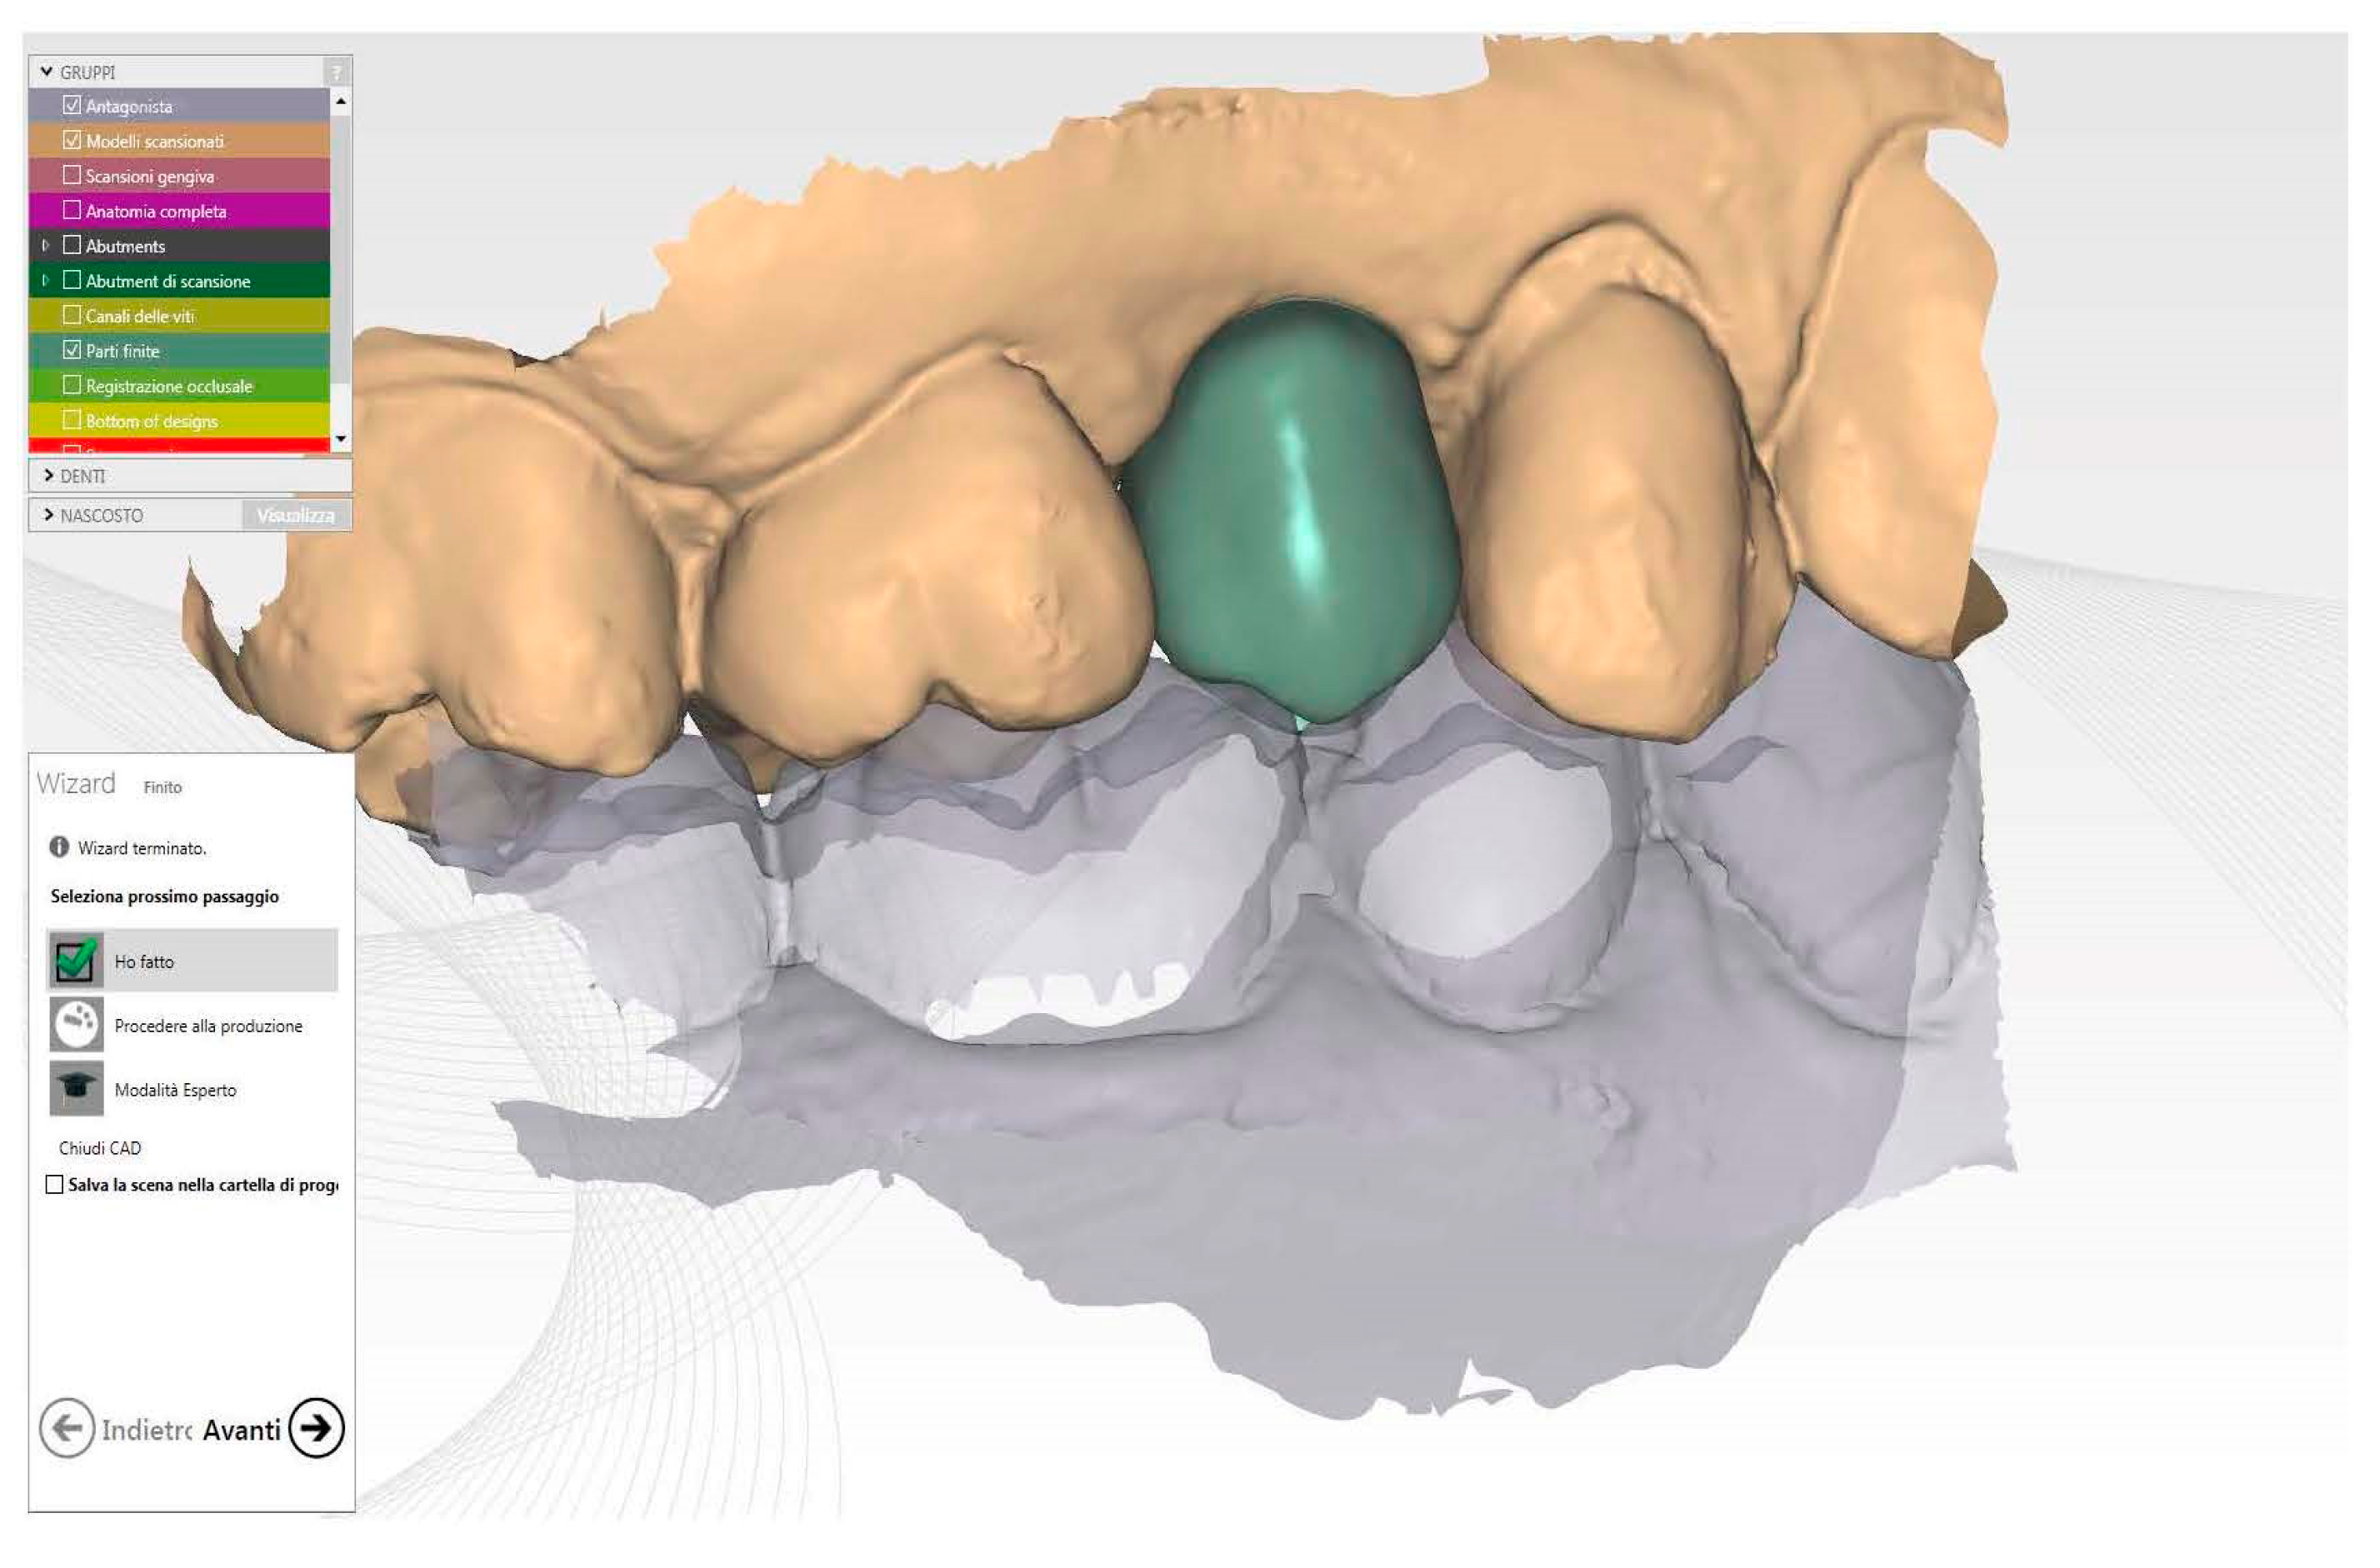

2.7. Customized Healing Abutment and Final Crown

The custom-made healing abutment was fabricated using advanced Computer-Aided Manufacturing (CAM) techniques. The abutment was precisely milled from a solid block of high-quality Polymethylmethacrylate (PMMA) (IESS, Pozzuolo del Friuli, UD, Italy), which had a minimal monomer residue of less than 0.02%, ensuring excellent biocompatibility and durability. The intricate CAD design process was carried out using state-of-the-art software (Performa, Pozzuolo del Friuli, UD, Italy), which allowed for the seamless integration of pre-operative (Figure 4) and intra-operative impressions to create the optimal design for the healing abutment [25,26].

The pre-operative impression of the tooth scheduled for extraction served as the foundation for the provisional shape. The only modification made was a slight reduction in the occlusal plane to prevent any interference with the patient’s occlusion (Figure 5).

Figure 5.

Healing screw CAD modelling starting to future final crown shape.

To ensure the precise positioning of the implant, the intra-operative impression was utilized. The CAD software, using this crucial information, accurately positioned the virtual ti-base within the selected provisional, determining its ideal shape and orientation based on the correct coordinates. The finalized CAD file was then sent to a cutting-edge milling machine (Zfx Mill Inhouse X4, Zfx, Dachau, Germany) for fabrication. The healing abutment underwent a meticulous finishing and polishing process, taking great care not to interfere with the closure margins (Figure 6).